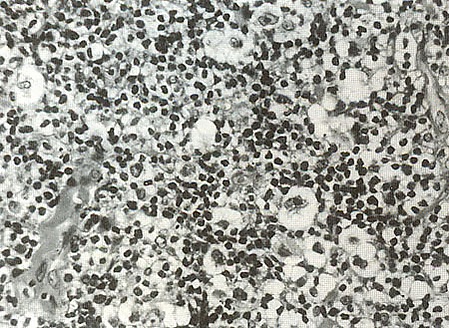

Обнаружение гигантских клеток Рид-Березовского-Штернберга и их одноядерных предшественников, клеток Ходжкина, в биоптате есть обязательный критерий диагноза лимфогранулематоза. По мнению многих авторов, только эти клетки являются опухолевыми. Все остальные клетки и фиброз есть отражение иммунной реакции организма на опухолевый рост. Главными клетками лимфогранулематозной ткани, как правило, будут мелкие, зрелые Т-лимфоциты фенотипа CD2, CD3, CD4 > CD8, CD5 с различным количеством В-лимфоцитов. В той или иной степени присутствуют гистиоциты, эозинофилы, нейтрофилы, плазматические клетки и фиброз. Соответственно различают четыре основных гистологических типа:

- Смешанноклеточный вариант — примерно 30 % случаев лимфомы Ходжкина. Наиболее частый вариант в развивающихся странах, у детей, пожилых людей. Чаще болеют мужчины, клинически соответствует II—III стадии болезни с типичной общей симптоматикой и склонностью к генерализации процесса. Микроскопическая картина отличается большим полиморфизмом со множеством клеток Рид-Березовского-Штернберга, лимфоцитов, плазмоцитов, эозинофилов, фибробластов.